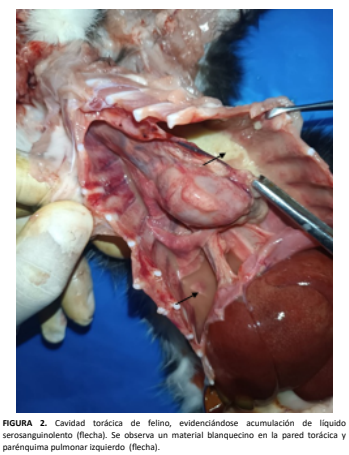

Medicina Veterinaria - Reporte de Caso